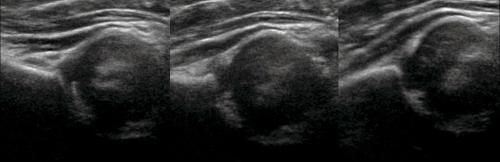

У новорожденного головка бедренной кости хрящевой плотности, что позволяет оценивать вертлужную впадину методом УЗИ. У детей старше 6 месяцев возможности ультразвука ограничены из-за окостенения краев впадины и частично головки.

Младенец лежит на спине или на боку. Бедро оценивают в нейтральном (15-20°) и согнутом (90°) положениях. Линейный датчик 7-15 МГц располагают в проекции большого вертела параллельно (1) или перпендикулярно (2) поясничному отделу позвоночника.

На третьем этапе тазобедренный сустав сканируют в поперечной плоскости. В случаях нестабильности, подвывиха или вывиха определяют кпереди или кзади смещается головка при пробе Барлоу-Ортолани.